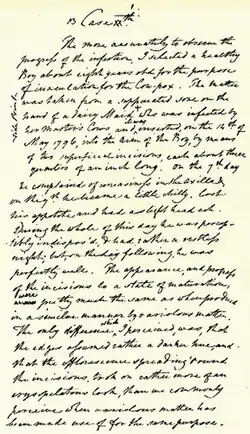

Jenner postulated that the pus in blisters from sufferers of cowpox (a disease similar to smallpox but much less virulent) protected them from smallpox. On 14 May 1796, Jenner tested his hypothesis by inoculating James Phipps, the eight-year-old son of Jenner's gardener. He scraped pus from cowpox blisters on the hands of Sarah Nelmes, a milkmaid who had caught cowpox from a cow called Blossom[35] (whose hide now hangs on the wall of the St. George's Medical School library, now in Tooting, London). Phipps was the 17th case described in Jenner's first paper on vaccination.[36]

Jenner inoculated Phipps in both arms that day; this led to a fever and some uneasiness but no full-blown infection. Later, Jenner injected Phipps with variolous material, the routine method of immunization at that time and again no disease followed. The boy was later challenged with variolous material and again showed no sign of infection. There were no unexpected side effects, and neither Phipps nor any other recipients underwent any future 'breakthrough' cases.

US physician Donald Hopkins has written, "Jenner's unique contribution was not that he inoculated a few persons with cowpox, but that he then proved [by subsequent challenges] that they were immune to smallpox. Moreover, he demonstrated that the protective cowpox pus could be effectively inoculated from person to person, not just directly from cattle."[39] Jenner successfully tested his hypothesis on 23 additional subjects.

Jenner continued his research and reported it to the Royal Society, though the initial paper was not published. After revisions and further investigations, he published his findings on the 23 cases, including his 11-month-old son Robert.[40] Some of his conclusions were correct, some erroneous; modern microbiological and microscopic methods would make his studies easier to reproduce. The medical establishment deliberated at length over his findings before accepting them. Eventually, vaccination was accepted, and in 1840, the British government banned variolation – the use of smallpox to induce immunity – and provided vaccination using cowpox free of charge (see Vaccination Act).